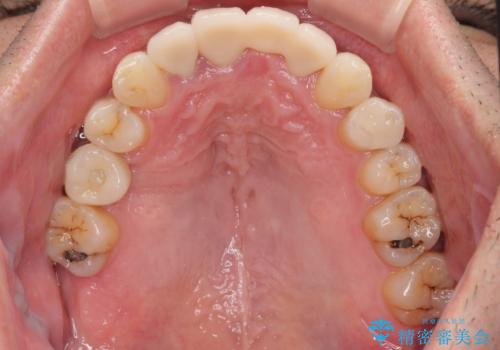

- むし歯治療途中で放置された歯が多く、スペースができたり歯が寄って来たりしているのを気にして来院された患者様です。

矯正治療を行いながら、欠損部はインプラントによる補綴治療を希望されたため、補助装置を用いたワイヤー矯正によりスペースを確保しながら歯列を整え、適宜インプラントを埋入していくこととしました。

上顎前歯もインプラントを希望していらっしゃいましたが、両隣の歯根が近接しており、インプラントは困難と判断したためオールセラミックブリッジによる補綴治療を前提として治療を開始することとしました。